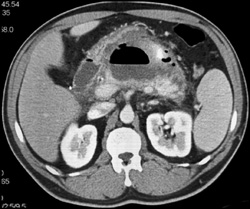

Pancreatic Abscess